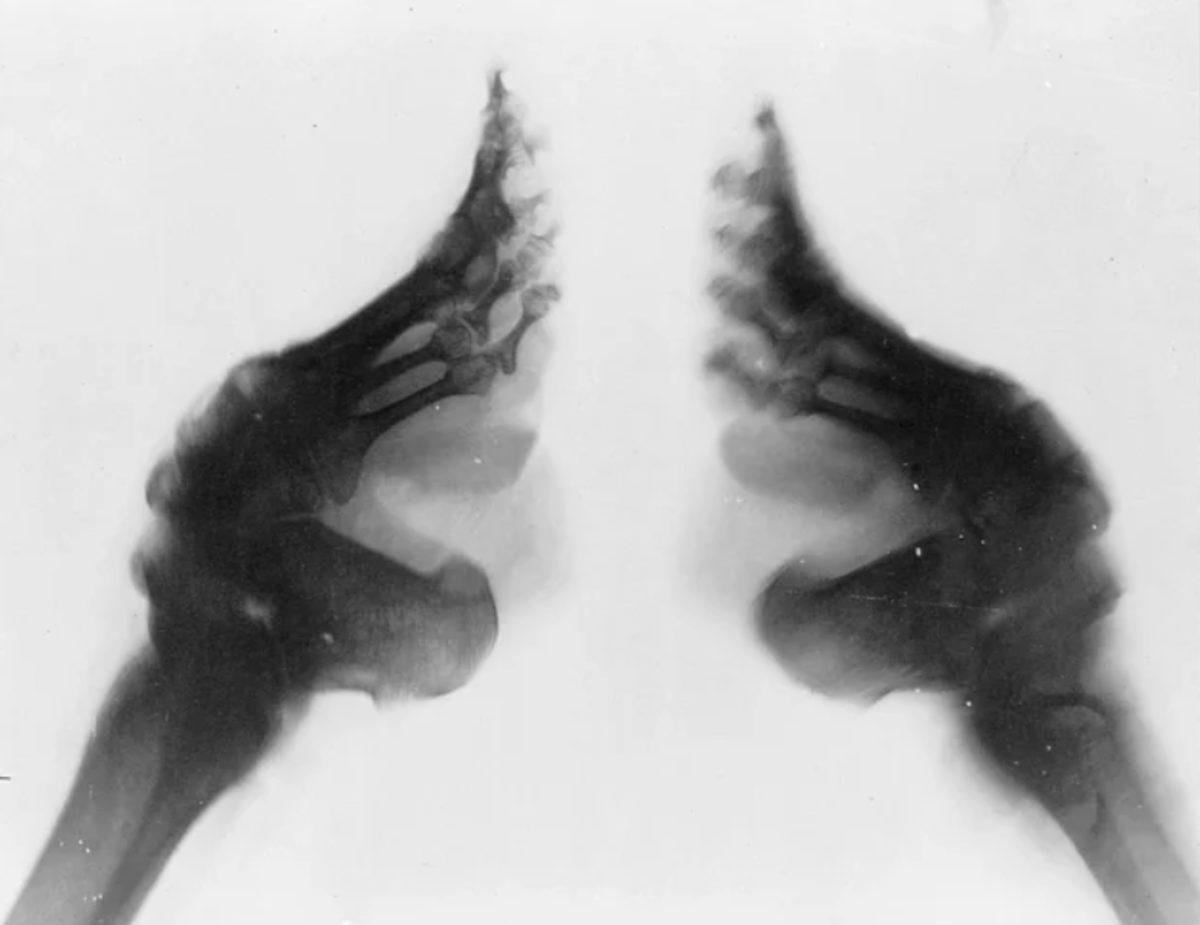

2. Çin'in ayak bağlama geleneğinin altında yatan tek neden çekici görünmek değildi.

Lotus ayak olarak da bilinen ayak bağlama geleneği, Çin'de yüzyıllar boyunca devam etmişti. Küçük ayakların daha çekici olduğu düşünüldüğünden küçük yaşlarda kız çocuklarının ayak kemikleri kırılıyor ve son derece küçük ayakkabılar içinde gezdirilerek küçük ayaklı olacaklarına emin olunuyordu. Kadınlar da bu acı dolu eylemi, toplum baskısı nedeniyle kabul ediyordu ve gelenek bir türlü bitmek bilmiyordu. 20. yüzyılın ortalarına doğru ancak terk edilen bu gelenek, yapılan araştırmalara göre sadece görsel kaygılar gütmüyordu. Nedenlerinden biri, kız çocuklarını yürüyemeyecek hale getirmek ve böylece evlerinde kalmalarına neden olarak dikiş nakış gibi işlerle uğraşmalarını sağlamaktı.